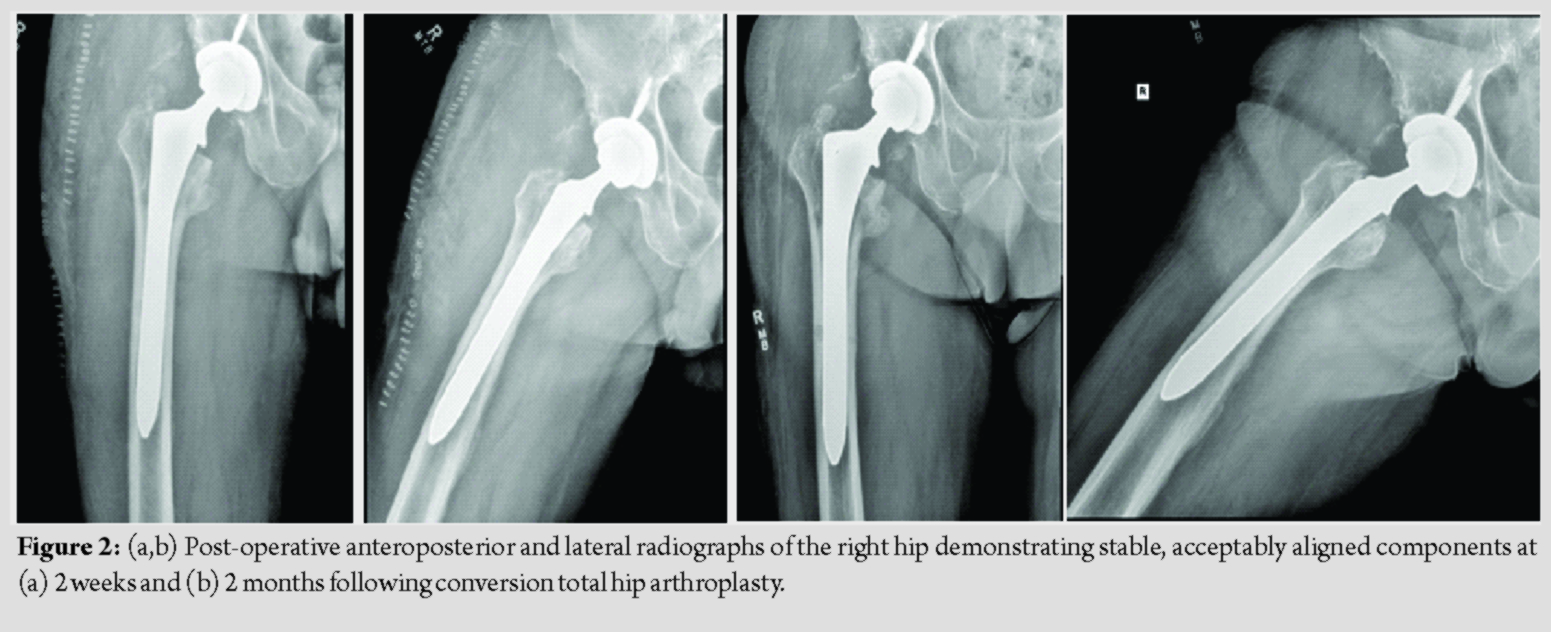

The patient was placed on the pre-established protocol during and after the surgery. He was cleared by physical therapy on post-operative day 1, and plans were made for discharge to home with a rolling walker. The patient was observed closely for signs of bleeding, and he remained asymptomatic throughout his hospital course. The patient’s hemoglobin and hematocrit did decrease to 8.0 g/dL and 24.6% before stabilizing, and no transfusion was necessary. Ultimately, the patient was discharged to home in stable condition on post-operative day 3, shortly after finishing nine doses of IV TXA per the previously established protocol. Follow-up was obtained at 2 weeks, 2 months, 5 months, and 10 months, with post-operative radiographs obtained at 2 weeks and 2 months (Fig. 2). The patient continued to progress to weight-bearing as tolerated without issue. Follow-up X-rays demonstrated stable and well-aligned components. His pre-operative pain improved dramatically. Despite some mild stiffness and a small leg length discrepancy, the patient’s overall clinical status improved significantly and he remains very satisfied with the outcome of his surgery. He did not have any bleeding-related complications throughout his perioperative course. At 10 months, the patient reported no complications, and he noted that he was back to full activity including hiking and snowshoeing without pain or other noticeable symptoms.